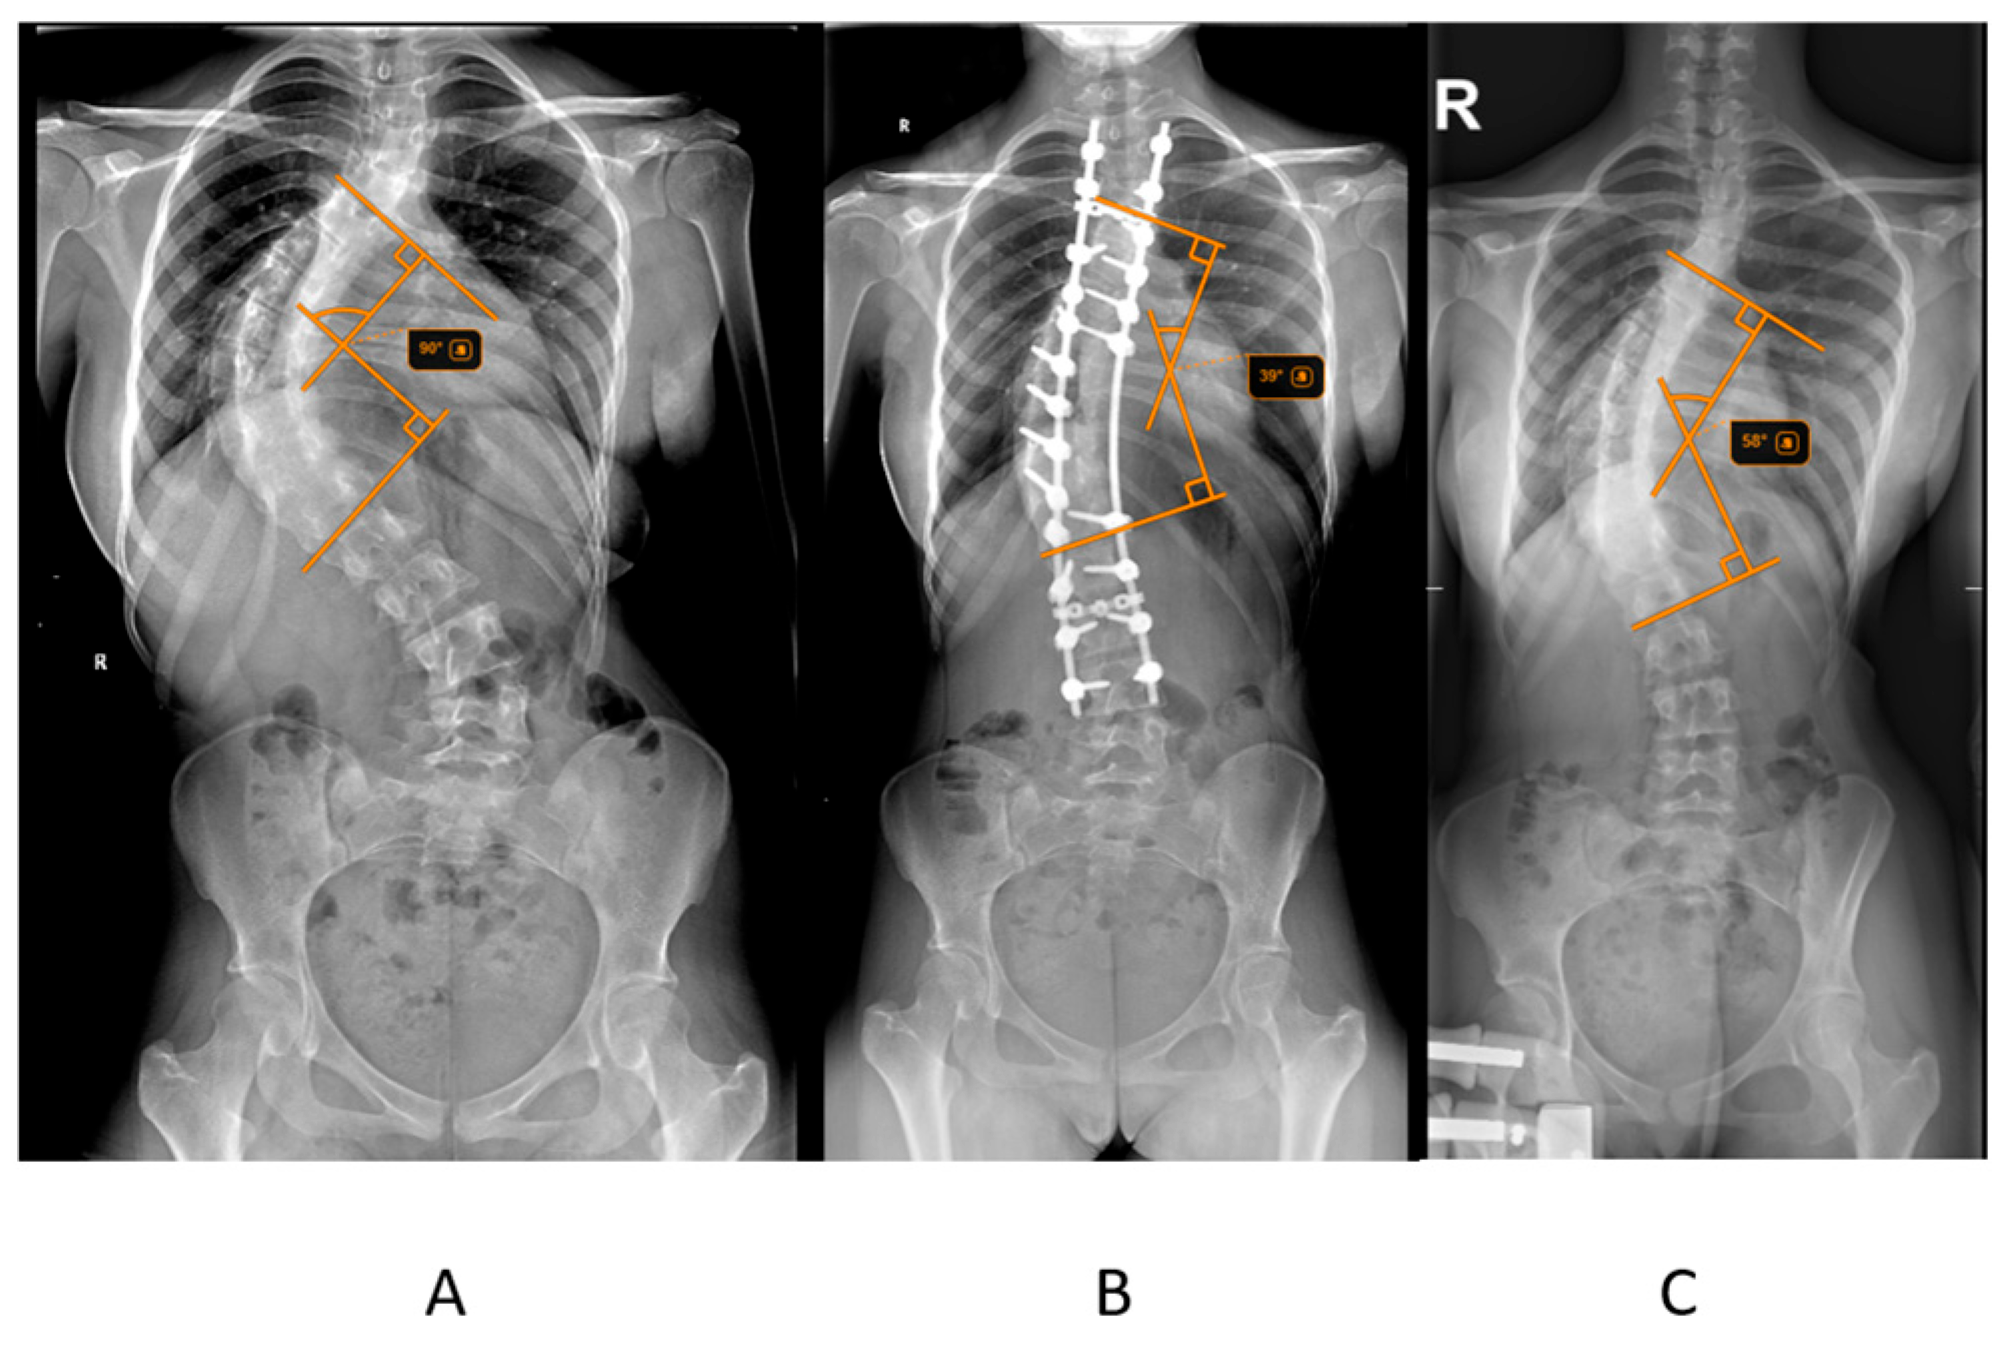

The primary outcome measured was postoperative Cobb angle improvement, calculated as the difference between the initial Cobb angle and the postoperative Cobb angle (Figure 1). The percentage reduction in Cobb angle after halo traction was also assessed. Radiographic measurements, including the Cobb angle and Risser score, were obtained from pre-traction, post-traction, and postoperative radiographs. The Risser score, which assesses skeletal maturity based on the ossification of the iliac crest, was determined from pelvic radiographs. Radiographic measurements, including the Cobb angle and Risser score, were obtained from pre-traction, post-traction, and postoperative radiographs. To ensure reliability, all Cobb angle measurements were independently performed by two orthopedic observers, and in cases of discrepancy greater than 5°, the average of the two measurements was used for analysis.

Figure 1. Radiological assessment of a patient from the study group diagnosed with adolescent idiopathic scoliosis. (A) Standing anteroposterior (AP) radiograph of the spine taken prior to the initiation of traction, showing the baseline curvature. (B) Standing AP radiograph after halo-gravity traction, demonstrating partial correction and increased spinal alignment. (C) Standing postoperative AP radiograph illustrating the final spinal alignment following surgical correction and instrumentation.